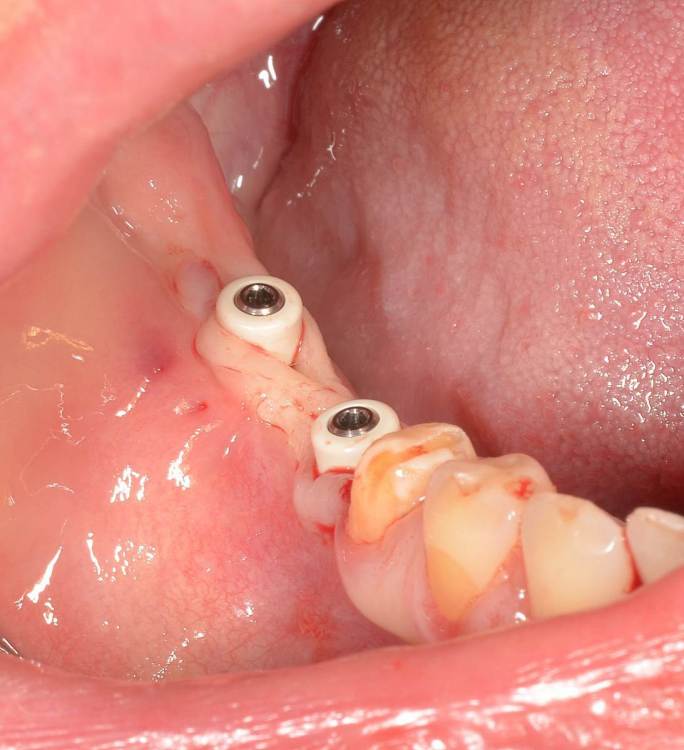

Большой Зеленый Опубликовано 7 ноября, 2022 Поделиться Опубликовано 7 ноября, 2022 Обратите внимание на даты 2 Ссылка на комментарий